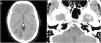

Figure 2.

Axial 3D TOF MRI angiography sequence performed at 3 months, showing a linear filling defect in the inferior third of the basilar artery (A) and a reconstruction showing this alteration, which may correspond to an incomplete fenestration (B).

As the patient’s clinical symptoms improved, he was discharged home and recommended monotherapy with acetylsalicylic acid, statins, and control of vascular risk factors. A follow-up angiography study consisting of a non-contrast 3 T MRI study with 3D TOF sequences was performed at 3 months, revealing the same alteration and no signs of intramural haematoma, aneurysm, or vessel stenosis suggesting basilar dissection,1 but rather an anatomical variant (incomplete fenestration) or septum (basilar web) (Fig. 2B).